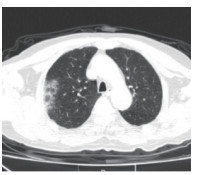

2.5 胸部CT结果入院时,为所有患者进行了胸部螺旋CT检查,47例(71.2%)患者表现为双侧多发性斑片样和磨玻璃样混浊,典型影像学表现见图 1,19例(28.8%)患者表现为单侧肺炎,典型影像学表现见图 2。

| 图 1 双肺感染 Fig 1 Bilateral lung infection |

在入院治疗3 d后,再次对所有患者复查了胸部螺旋CT。39例(59.1%)患者肺部感染灶有不同程度增多,27例(40.9%)患者肺部感染灶无明显进展。